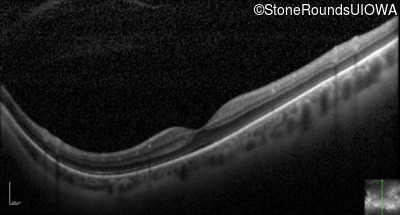

Optical Coherence Tomography - Right - 20/25 -3

Exemplar / OCT Stack